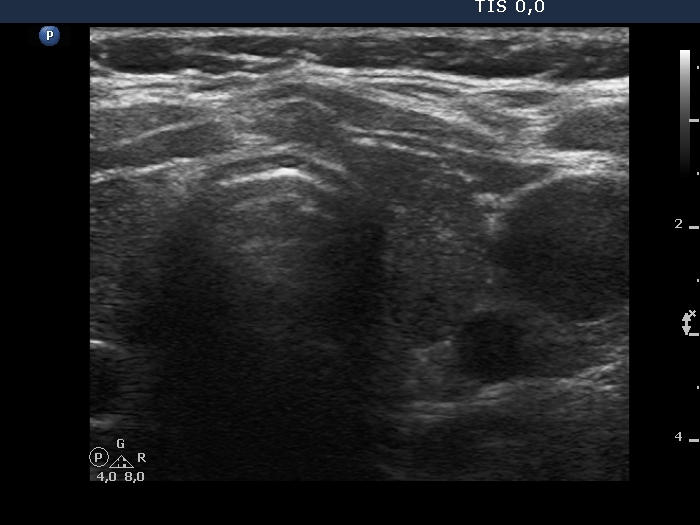

Examination in 2013 (first row of images):

Ultrasonography. The thyroid was minimally/moderately hypoechoic and had several discrete minimally/moderately hypoechoic lesions.

Cytology was performed from the lesion in the central part of the right lobe and resulted in Hashimoto's thyroiditis.